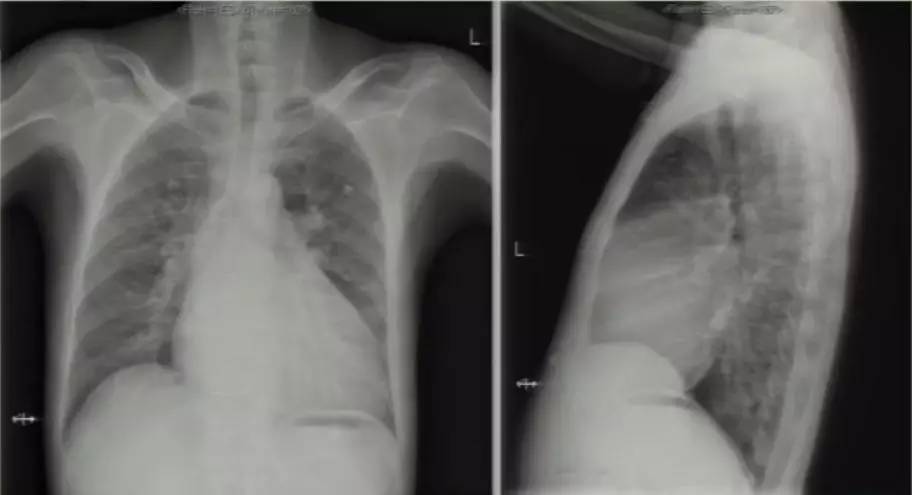

进一步完善相关检查:胸片提示双肺淤血,肺血增多,升主动脉及主动脉结增宽,肺动脉段平直,全心增大,心胸比0.63(图6)。复查超声心动图可见LA 58 mm,LV 53 mm,LVEF 60%,RV 41 mm;房间隔卵圆孔回声分离3 mm,后下部薄弱,探及数处回声脱落,大者约18 mm;二尖瓣前叶发育异常,收缩期瓣体向左房弯曲,致对合不拢。超声提示先天性心脏病(先心病)、Ⅱ孔型房间隔缺损(多发)、卵圆孔未闭、房水平左向右分流 ,二尖瓣脱垂并中大量反流,三尖瓣少中量反流,肺动脉高压49 mmHg。心脏CT提示先心病、房间隔缺损(下腔型),二尖瓣脱垂,双房右室扩大,少量心包积液(图7)。

图6